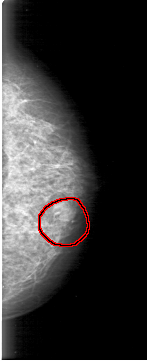

FILE: D_4038_1.LEFT_MLO.OVERLAY

TOTAL_ABNORMALITIES 1

ABNORMALITY 1

LESION_TYPE MASS SHAPE OVAL MARGINS OBSCURED

ASSESSMENT 0

SUBTLETY 4

PATHOLOGY BENIGN

TOTAL_OUTLINES 1

BOUNDARY

FILE: D_4038_1.LEFT_CC.OVERLAY